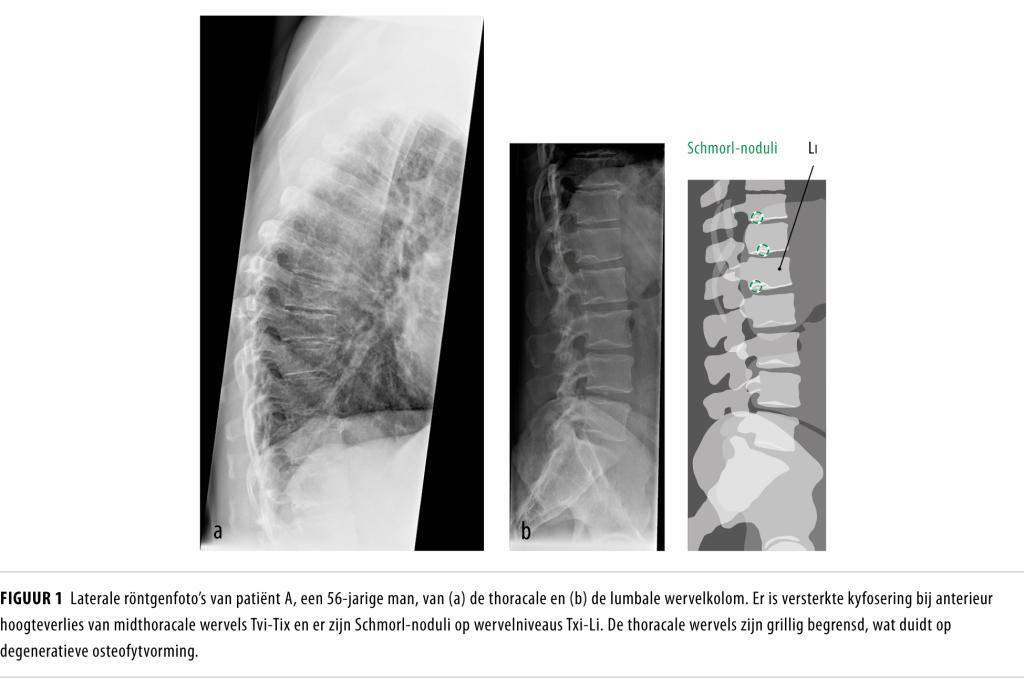

From www.ntvg.nl

Osteoporotische wervelfracturen of ziekte van Scheuermann? NTvG Rug Ziekte Van Scheuermann Meestal hebben jongeren met de ziekte van scheuermann alleen een bollere rug en verder geen klachten. Wat is de ziekte van scheuermann? De ziekte van scheuermann is een groeistoornis in het borstgedeelte van de wervelkolom. Dit komt met name voor wanneer er een forse kromming is en er een zichtbaar ronde rug ontstaat. De ziekte van scheuermann is een aandoening. Rug Ziekte Van Scheuermann.